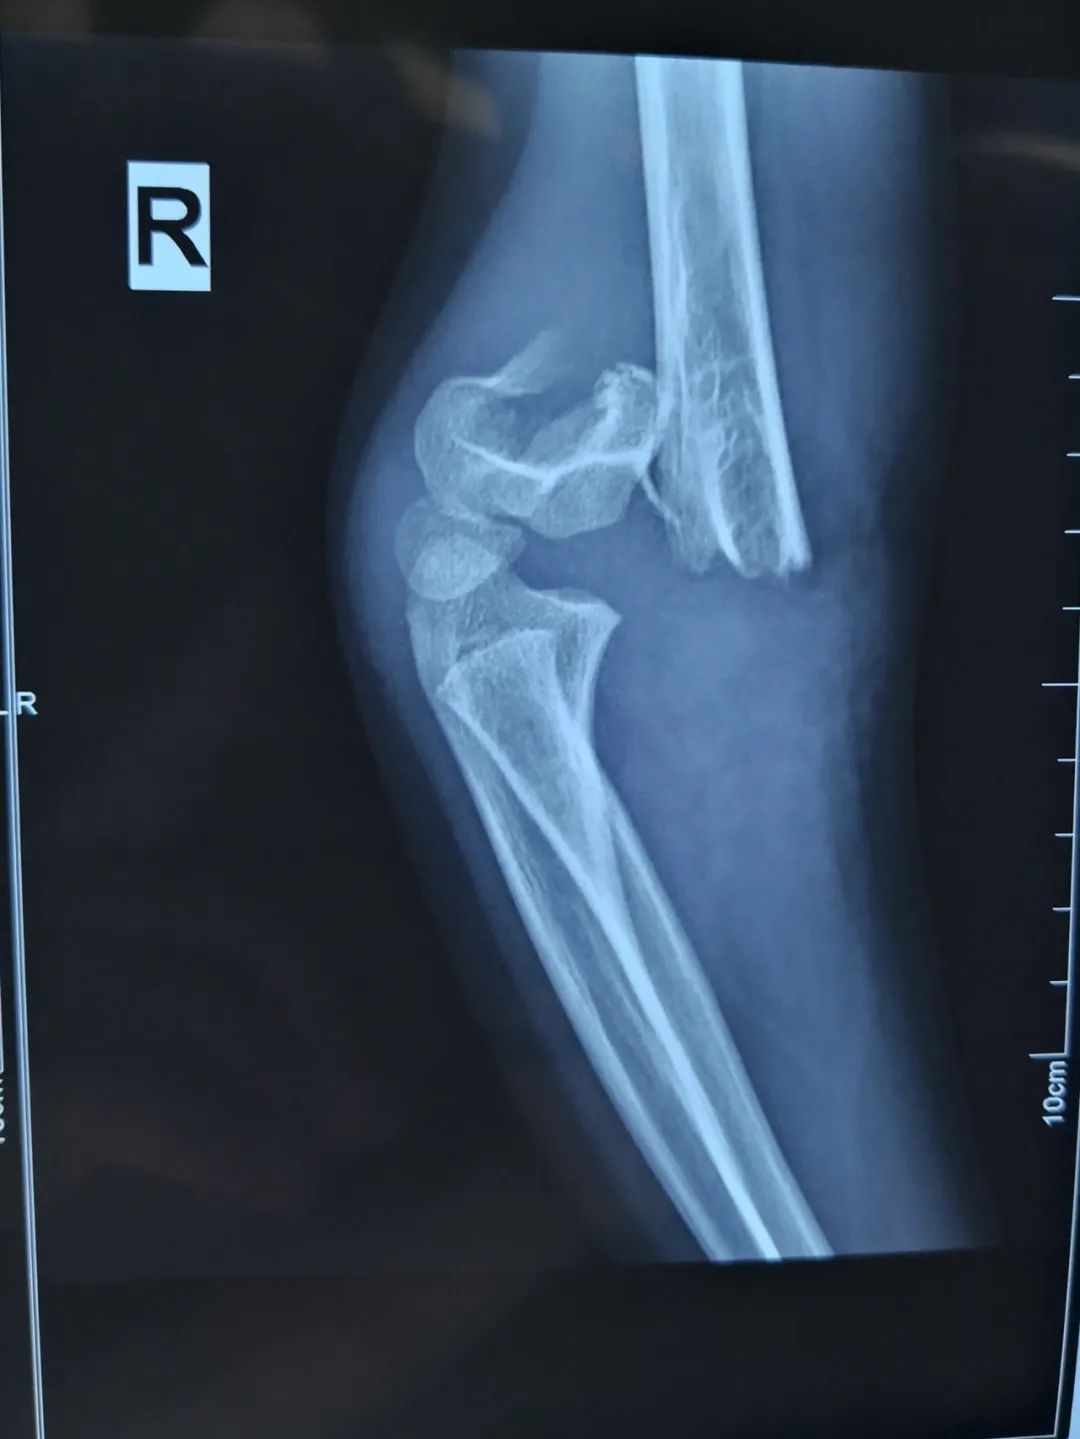

近日,淄博市第七人民医院连续接诊4例因使用平衡车摔伤的儿童,其中1例受伤较重,右侧胳膊骨折伴桡神经损伤。另2例骨折给予手法复位闭合穿针内固定。还有1例皮外伤给予清创包扎后离院。

刘法银医生介绍称,经检查,童童诊断为右侧肱骨髁上骨折,软组织挫伤重,伴桡神经损伤,给予‘桡神经探查术+切开复位内固定术’。

“对于另外2例骨折患儿,因未造成神经损伤,给予C臂透视下手法复位闭合穿针内固定手术,不用切口,创伤小,恢复快,术后四周门诊拔出钢钉,免除二次手术取内固定。”刘医生说道。